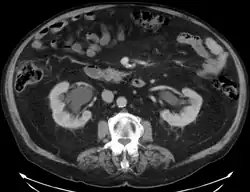

Tomografia komputerowa raka pęcherza moczowego. Guz oznaczony niebieską strzałką, czerwoną strzałką oznaczono zakrzepicę lewej żyły biodrowej zewnętrznej

Postawione podczas cystoskopii podejrzenie raka inwazyjnego lub potwierdzenie histopatologiczne obecności raka inwazyjnego wskazują na konieczność wykonania tomografii komputerowej (TK) lub rezonansu magnetycznego (MRI) miednicy i brzucha w celu oceny zaawansowania choroby[151][152]. Celem wykluczenia rozsiewu do płuc wykonuje się zdjęcie rentgenowskie klatki piersiowej (RTG) lub tomografię komputerową klatki piersiowej[135].

Tomografia komputerowa

Tomografia komputerowa (TK) jest podstawowym badaniem obrazowym służącym do oceny zaawansowania raka pęcherza moczowego[153][154]. Tomografia komputerowa pozwala na dobrą dokładność diagnostyczną oceny obecności rozsiewu do narządów odległych i lokalnych węzłów chłonnych[153]. Czułość badania w zakresie rozpoznawania raka pęcherza moczowego jest oceniana na 85%, a swoistość 94%[155][154].

Nowotwór w zakresie pęcherza moczowego może być widoczny jako pogrubienie ściany narządu, które może ulegać wzmocnieniu kontrastowemu[156][157]. Badanie pomaga rozpoznać naciekanie tkanek okołopęcherzowych (T3), jednak nie umożliwia wiarygodnego rozróżnienia guzów nieinwazyjnych (Ta) od naciekających błonę mięśniową (T1)[158]. Ocena inwazji sąsiednich narządów (cecha T4) za pomocą TK może być trudna, szczególnie w przypadku podejrzenia nacieku pochwy i macicy, gdy oddzielająca je tkanka tłuszczowa jest cienka[156].